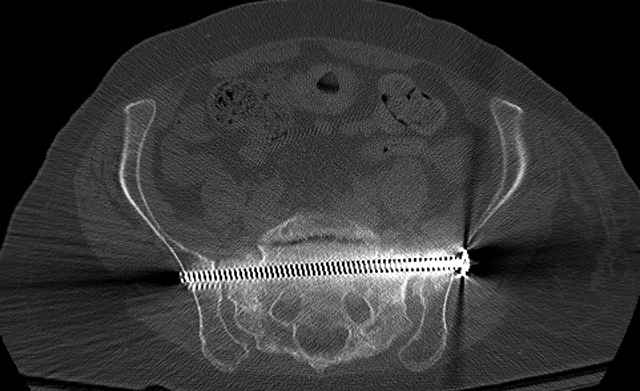

Percutaneous Fixation

(B) Ramus-Retrograde

2 TransIliac-TransSacral

Upper Segment